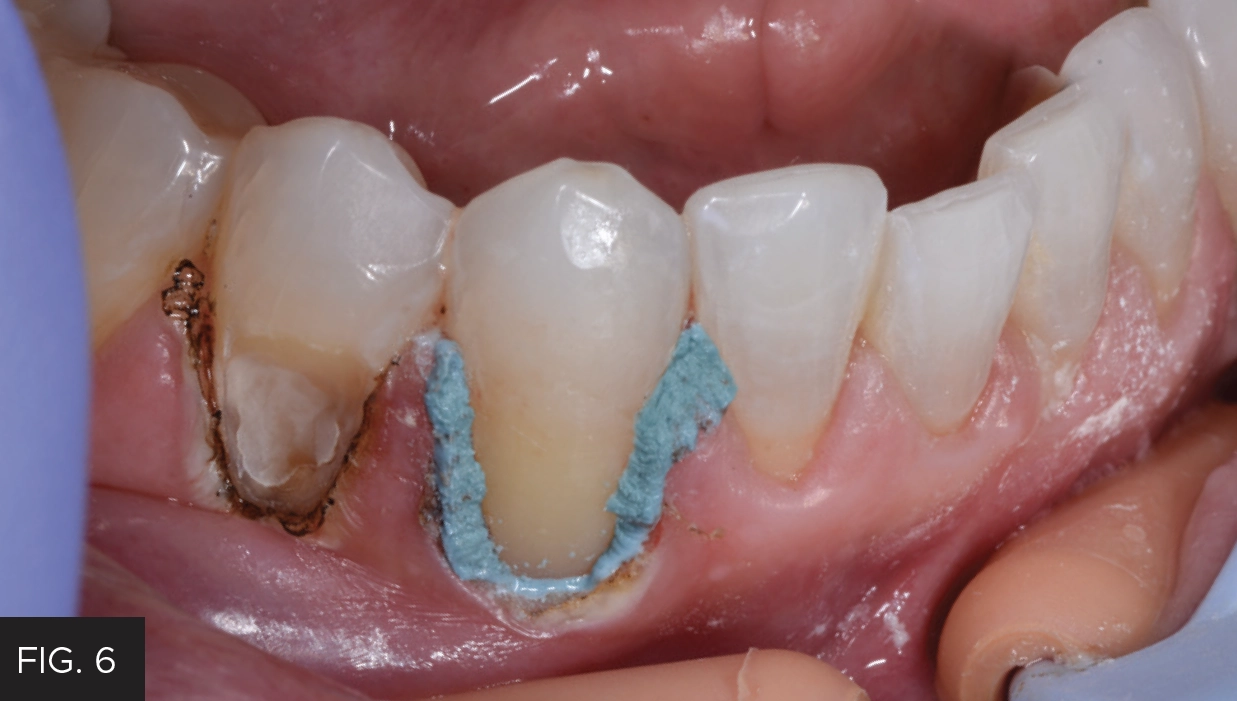

After complete decay removal, the deeper areas of the preparation were protected with Vitrebond™ (3M). (FIG. 6)